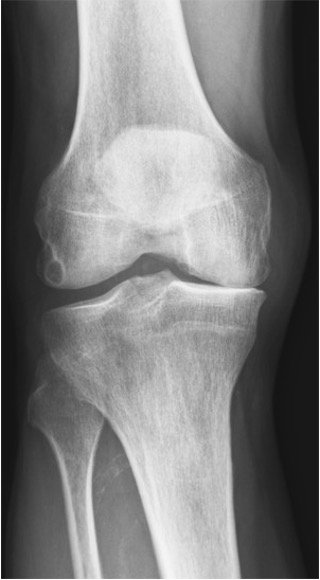

Artrose kneledd

Røntgen av medial kneartrose

Kliniske funn

Ved kneartrose redusert passiv bevegelighet i kapsulært mønster med mer redusert fleksjon enn ekstensjon, hard endefølelse

- Artrose: kapsulært mønster (fleksjon mer redusert enn ekstensjon), hard endefølelse, redusert passiv bevegelighet